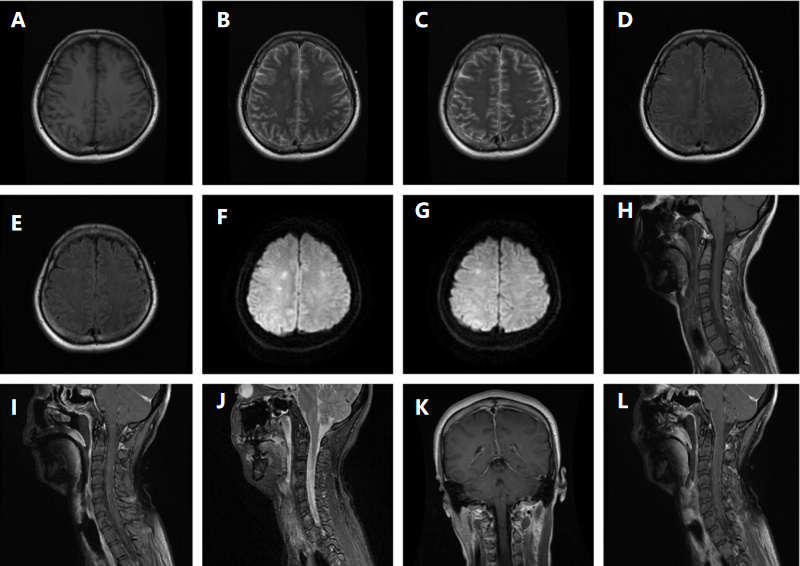

7月2日体温转正常,神志转清楚,但发现四肢肌力明显对称性减弱,医学研究委员会(MRC)总评分为0/60,上下肢肌张力稍微增高,全身感觉正常。复查腰椎穿刺检查,脑脊液压力135 mmH2O,脑脊液外观淡黄色,潘氏试验阳性,细胞计数63×106/L,单个核细胞100.0%,葡萄糖3.61 mmol/L(同期末梢指尖血糖9.3 mmol/L),氯125.9 mmol/L,蛋白定量1 399 mg/L; 动态脑电图提示:重度异常动态脑电图(图 2); 肌电图提示:左右胫前肌、左腓肠肌内侧头、右第一骨间肌未见明显纤颤、正尖波,轻重收缩募集相减少; 神经传导速度测定:左右腓总神经运动传导仅见微小波动,左右正中神经、左右尺神经、右胫神F波出现率降低或未引出; 重复神经电刺激未见明显异常。脑脊髓MRI提示:双侧额叶、右侧脑室后角旁白质及脑干多发异常信号并脑膜、脊膜强化,脑膜脑炎可能(图 3)。血清和脑脊液样本分别送检基于组织底物的间接免疫荧光法筛查三项、副肿瘤综合征18项抗体、自身免疫性脑炎21项抗体、中枢神经脱髓鞘7项抗体均为阴性; 血清周围神经病30项抗体中抗GT1a抗体IgM强阳性。修正诊断为CPN肺炎并ADEM和GBS重叠,予人免疫球蛋白(20 g/d,共5 d)和甲基强的松龙(80 mg/d,共3 d),然后口服泼尼松剂量[1 mg/(kg·d)],缓慢减少。治疗过程中发现颜面部肌肉瘫痪,口咽、颈部和上肢无力表现更为突出,患者在神志清楚,气道呛咳反射和咳嗽峰流速正常情况下因无法吞咽并气道保护能力差,拔管失败2次,随着治疗延续及康复干预,吞咽功能改善,气管插管17 d后才成功拔除气管插管。

| MRI: 双侧额叶皮层下白质区、右侧脑室后角旁白质,T1WI呈等、稍低信号(A),T2WI(B、C)、T2flair呈高信号(D、E),DWI呈稍高信号(F、G); 脑干见多发斑点、斑片状异常信号, T1WI呈等、稍低信号(H),增强后未见强化(I),T2WI呈高信号(J); 增强扫描硬脑膜可见硬化(K、L) 图 3 颅脑脊髓 |